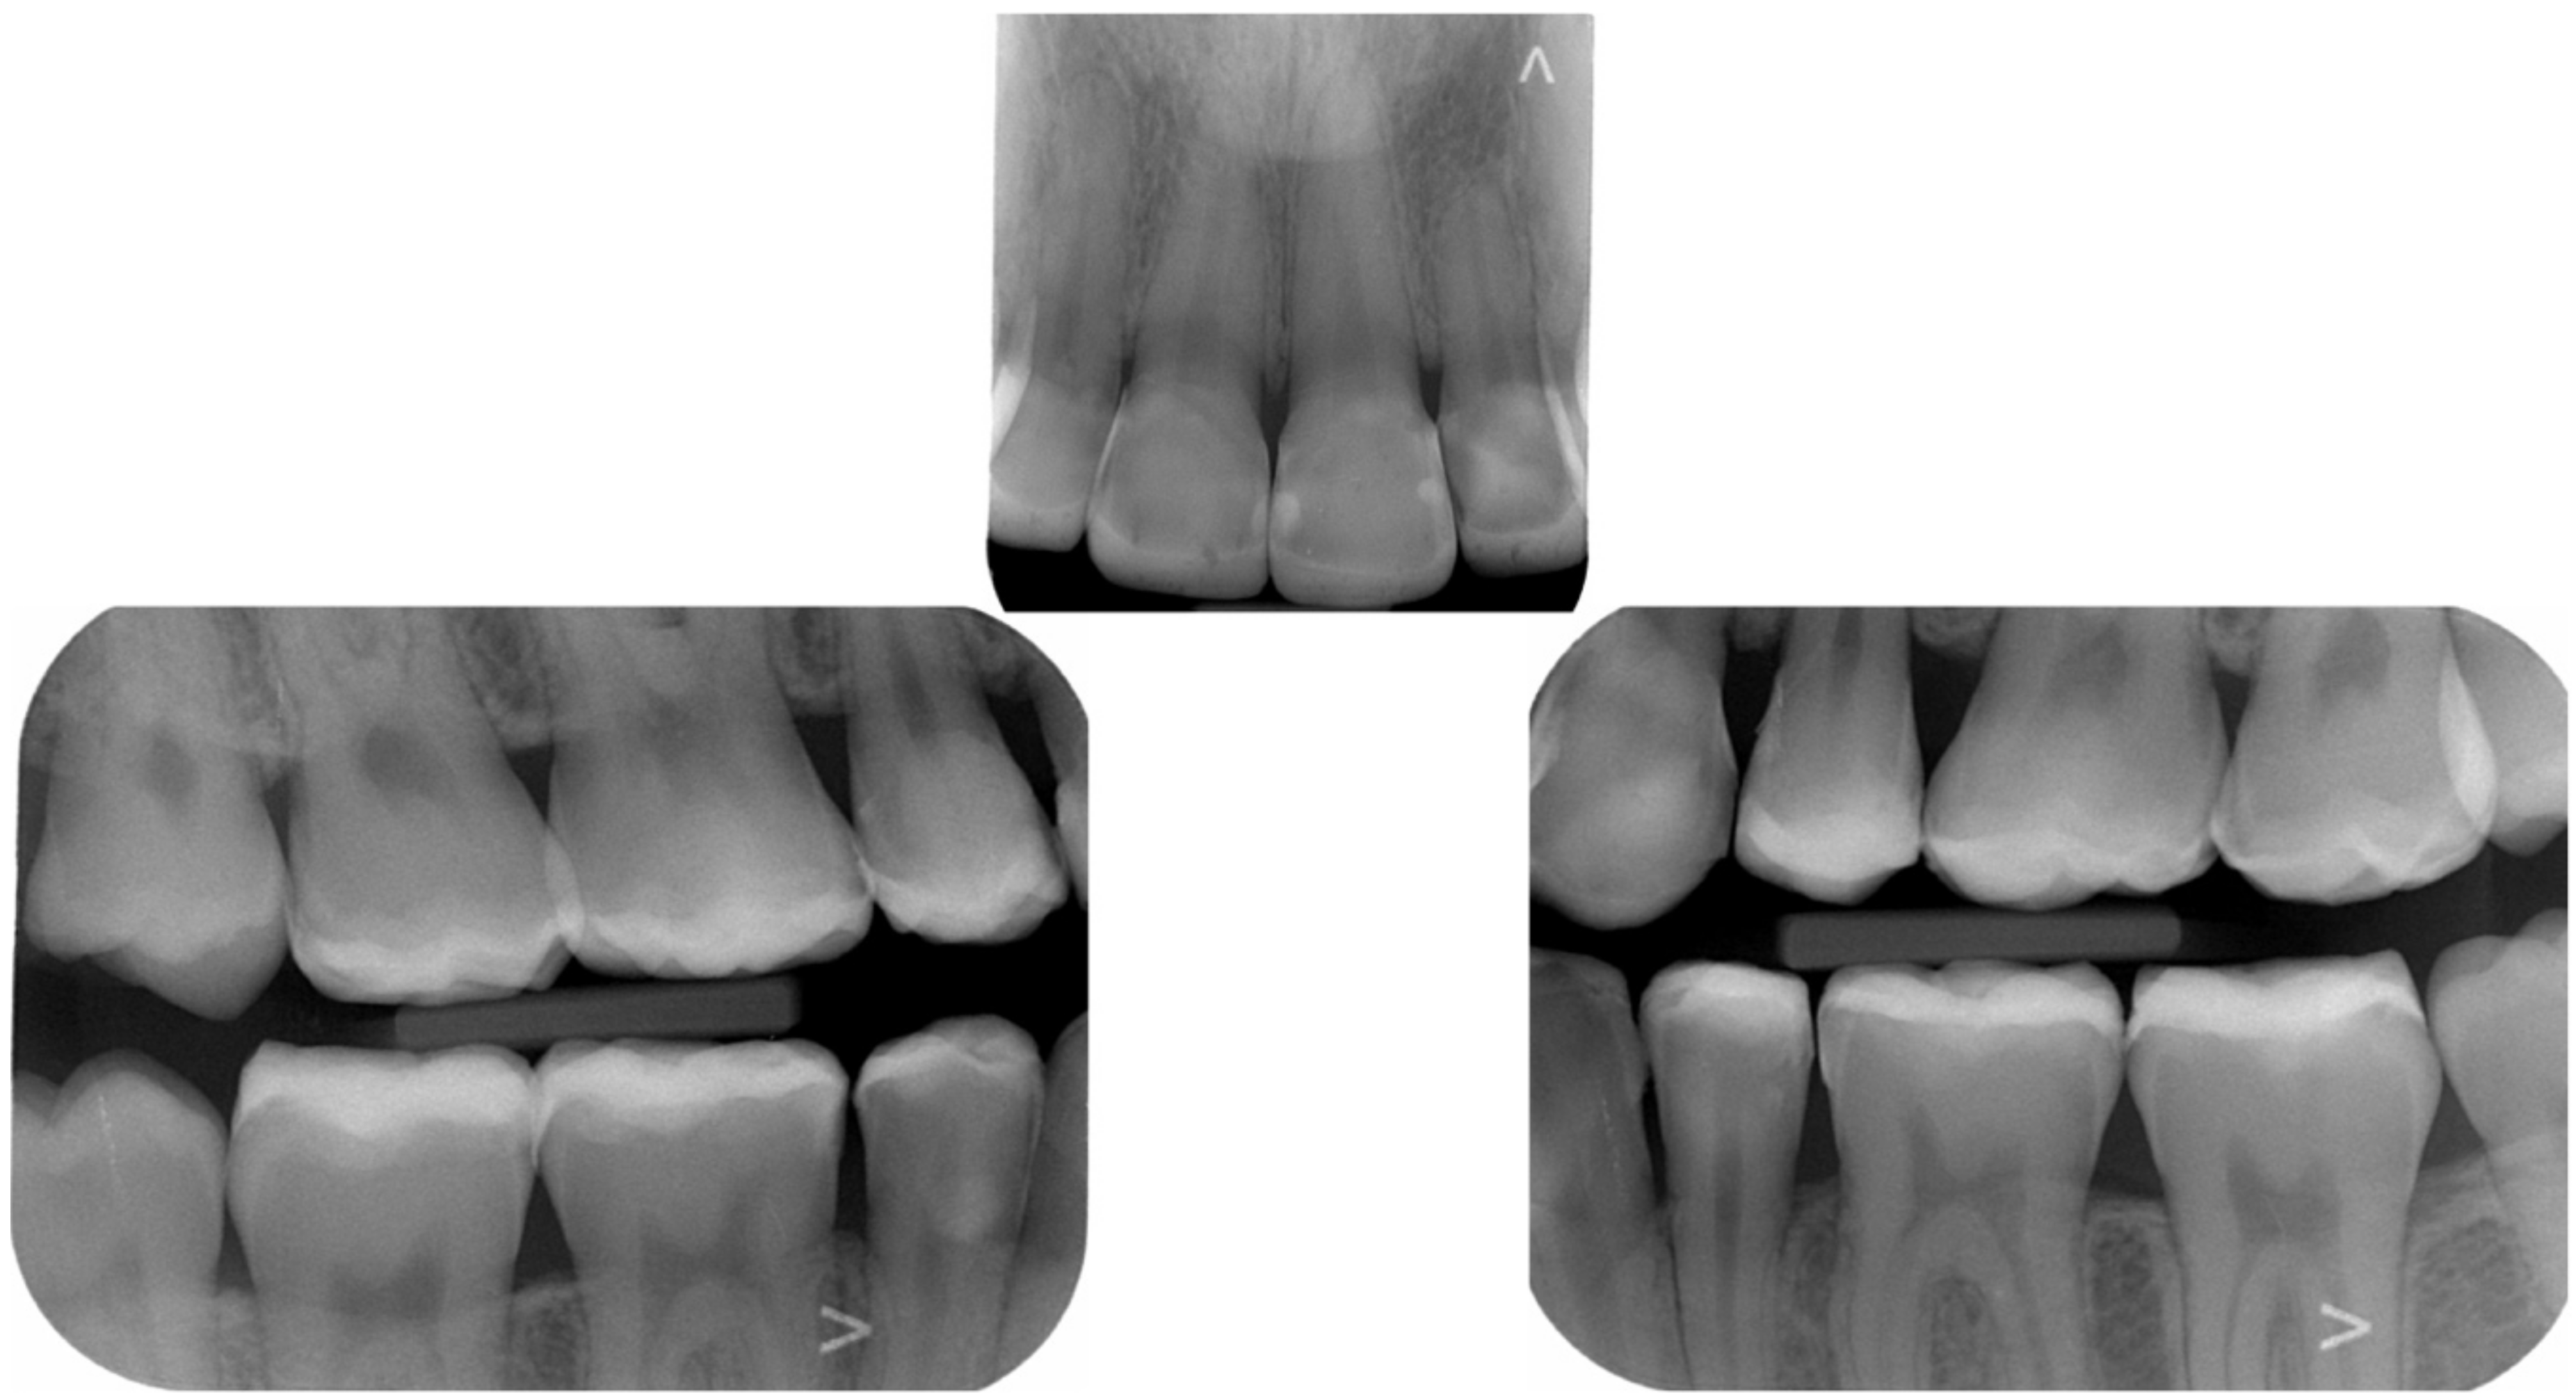

2. Clinical Report

2.1. Planning Phase